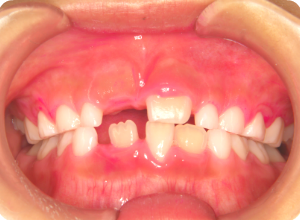

萌出したての乳歯や永久歯は歯質が未成熟な為、虫歯の原因となる菌の作り出す酸に対する抵抗力がとても弱く、虫歯にかかるリスクが大変高くなります。

①まずは歯磨きがキチンと出来ているか、赤く染めて検査します。

②磨き残しや汚れなどを、ブラシとラバーカップを使って落としていきます。

キレイになりました。

③それぞれのお口の大きさに合わせたトレーを使い、フッ素を塗布していきます。